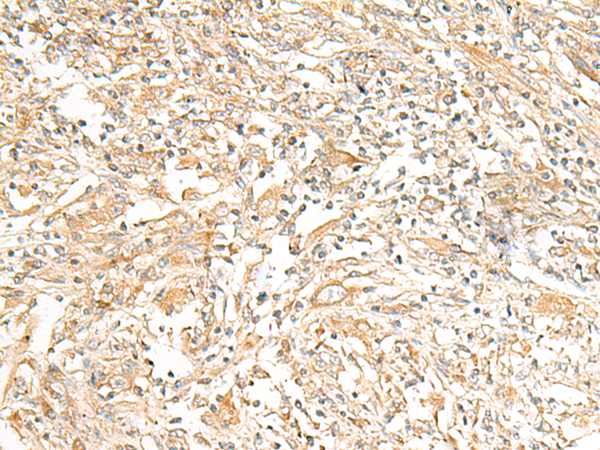

分类: 科研抗体货号: P13467别名: GLUT8; GLUTX1应用: WB反应种属: Human, Mouse, Rat

-